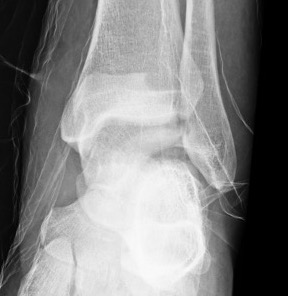

Xray / CT

Ensure no displacement / malalignment

Xrays

| AP | Lateral | Canale View |

|---|---|---|

| Entry point of the screws |

Evaluate neck reduction

|

Evaluates the neck reduction |

Lateral off articular surface Medial through articular cartilage |

Depth of screws |

Beam angled 75o to foot Foot 15o pronated |